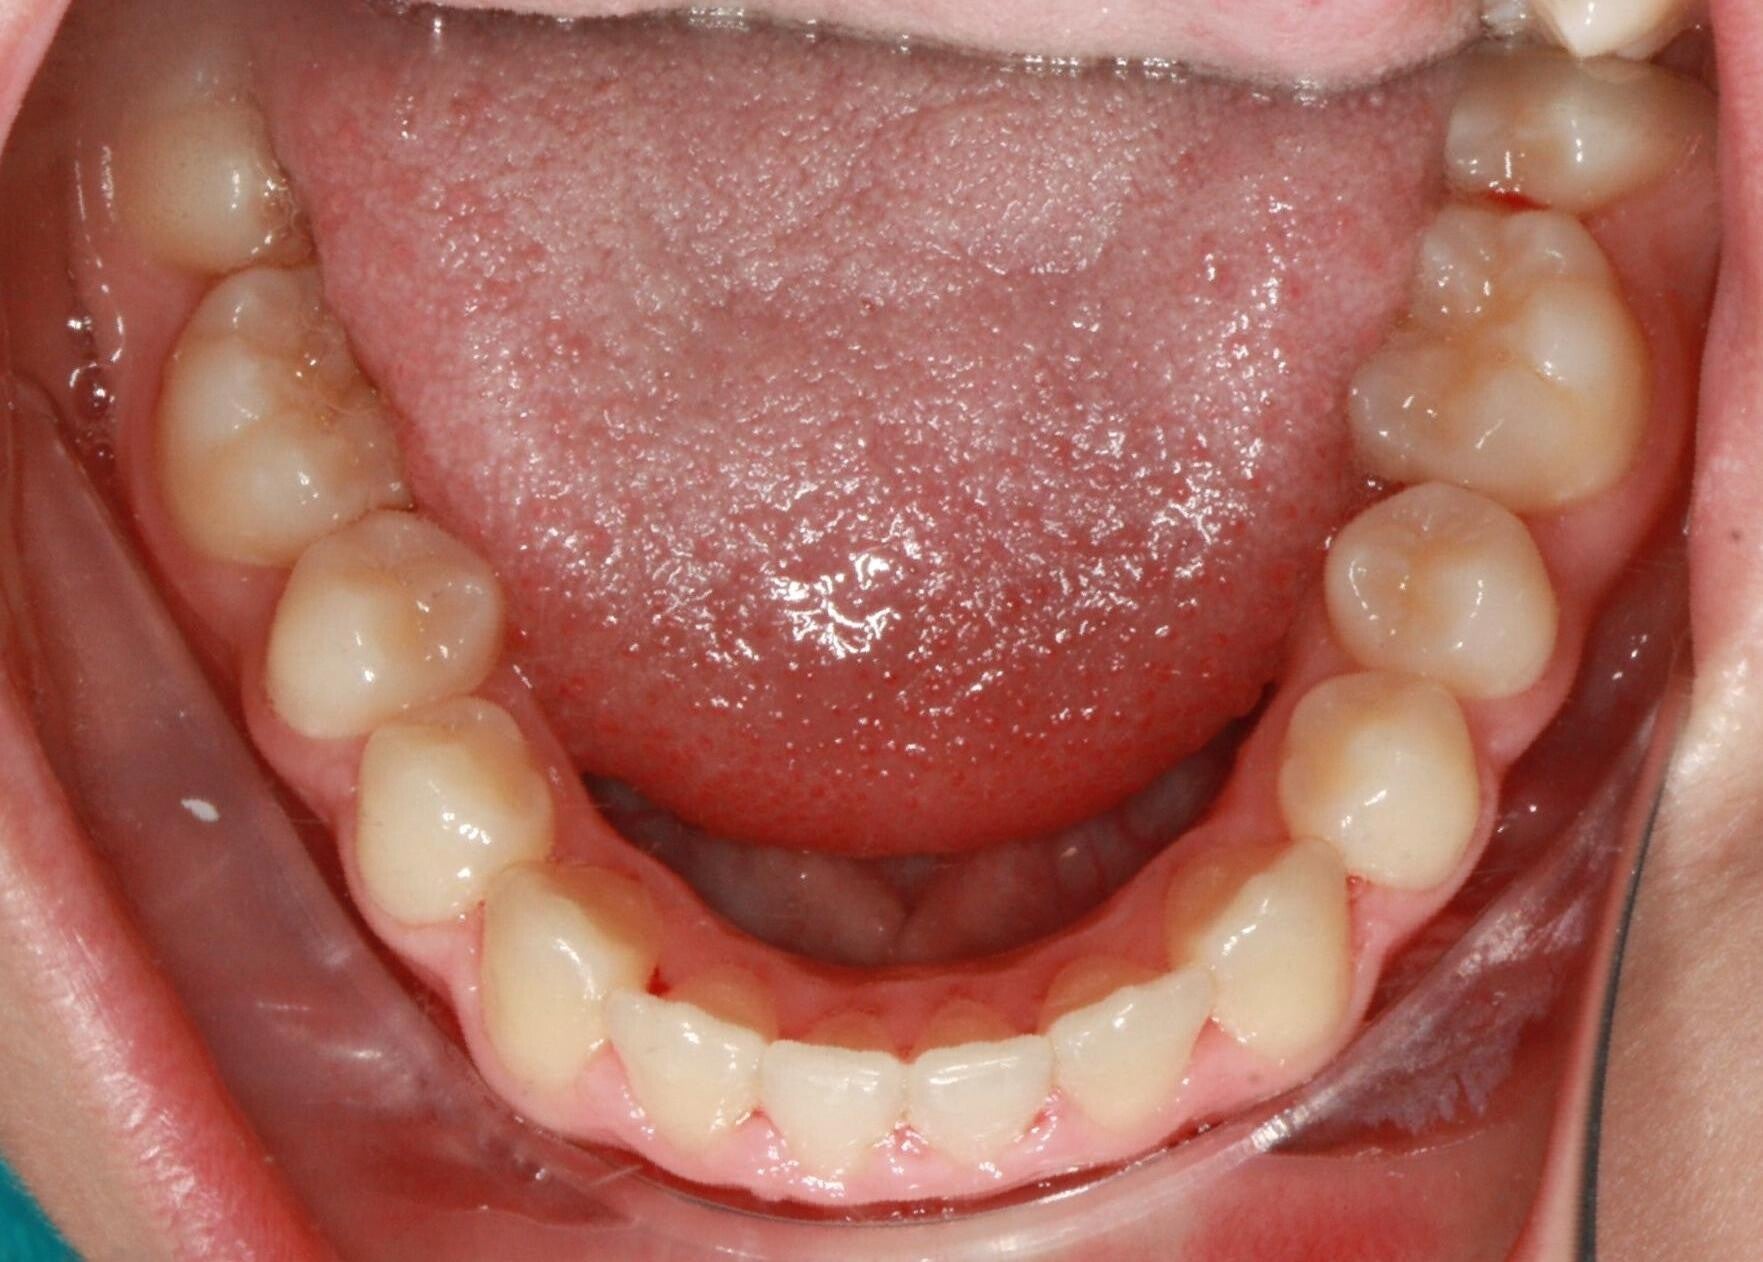

FOTO FINALI DOPO 24 MESI CIRCA DI TERAPA ORTODONTICA FISSA

PRIMA CLASSE CON AFFOLLAMENTO GRAVE SUPERIORE A SINISTRA CON PERDITA PRECOCE DEL SECONDO MOLARE INFERIORE SINISTRO

Abbiamo appena portato a termine questo caso che presentava in arcata superiore il primo premolare di sinistra completamente fuori arcata sovrapposto al secondo premolare ed il canino ruotato.

in arcata inferiore invece abbiamo estratto il secondo molare di sinistra perso per carie deostruente e mesializzato il terzo molare in modo da chiudere lo spazio e non ricorrere all'inserimento di protesi implantare.